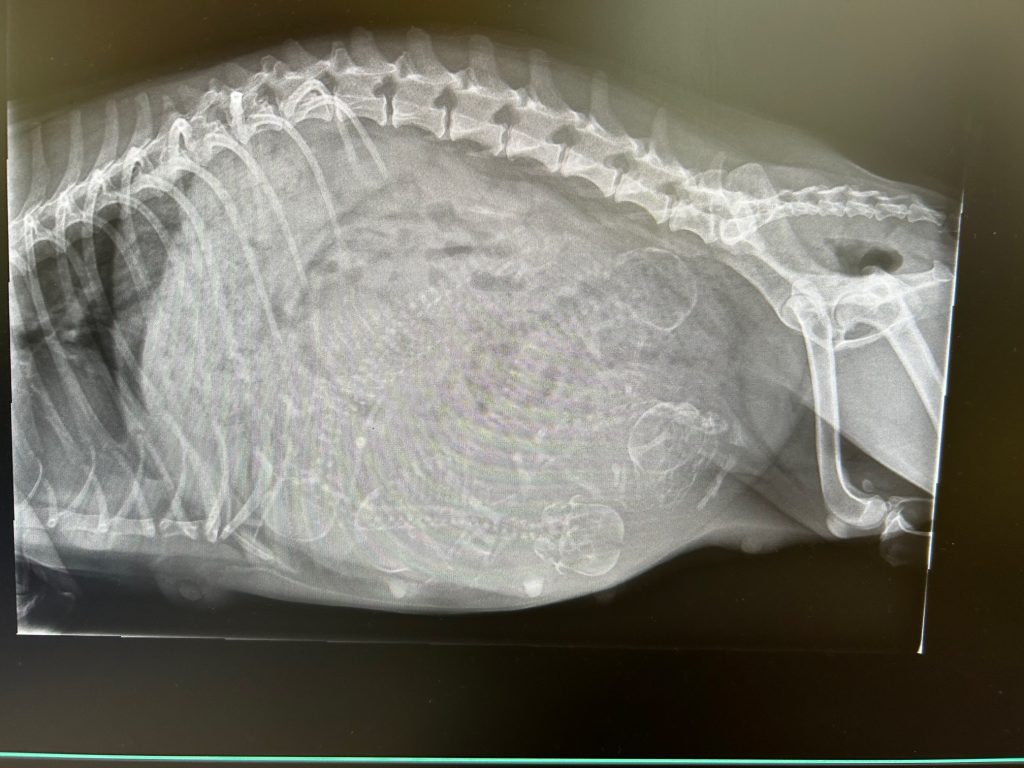

Auf dieser Seite folgen vor und nach der Geburt die ersten Bilder und Videos.

- Mädchen (rosa Halsband): 29.01.2025 13:50 Uhr / 162 g

- Junge (blaues Halsband): 29.01.2025 14:00 Uhr / 175 g

- Junge (grünes Halsband): 29.01.2025 14:35 Uhr / 172 g

- Junge (orangenes Halsband): 29.01.2025 14:52 Uhr / 158 g

- Mädchen (lila Halsband) :29.01.2025 15:08 Uhr / 144 g